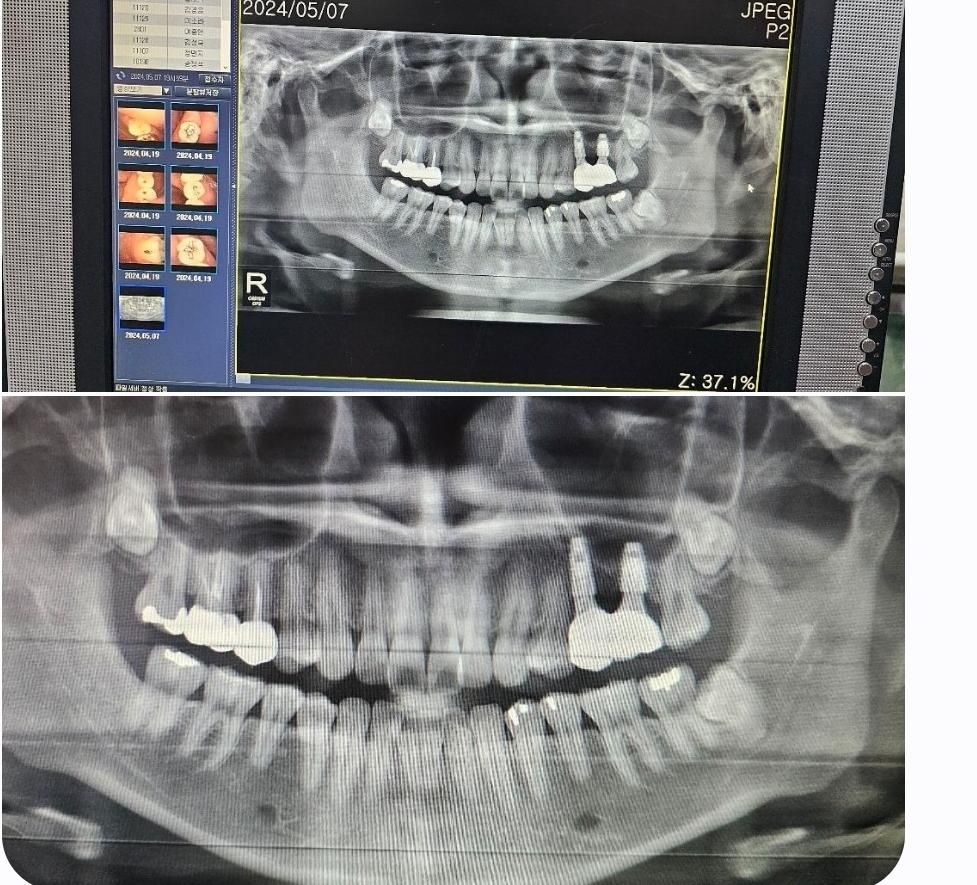

임플란트 엑스레이 사진 확인 부탁드립니다.

임플란트를 21년도 초에 했구요.

이번에 다른 치과에서 충치 진료 보다가

임플란트한 잇몸 부분이 검게 보여서

진료 부탁드렸는데 잇몸뼈가 다 녹았다 라면서

길어야 2~3년 밖에 더 못쓰게 쓸 것 같다고

얘기를 해주시더라구요.

그래서 수술했던 치과에 새로 찍은 엑스레이 사진과

함께 연락드렸더니 문제없어 보인다고 하시고..

뭐가 맞는건지 모르겠네요.

전문가님들의 답변 부탁드립니다.

임플란트 주위염으로는 보이지 않습니다. 혹시나 임플란트가 흔들리거나 해당 부위가 아프면 치과 다시 가면 됩니다.

일단은 엑스레이사진으로는 크게 염즈이 소견이 잇어 보이진 않습니다. 치료 받으신 치과에 가셔서 다시 진단을 받아보시고 혹시 염증이 나오거나 불편하시면 CT까지 찍어보시는게 좋을것같습니다.

사진으로만 봐서는 큰 이상이 없어 보입니다 특별한 불편감이 없다면 임플란트에 가해지는 힘을 약하게 해서 사용해 주는 것을 권유 드립니다

1. 정확한 판단을 위해 파노라마 사진 외 치근단 방사선사진도 필요해보입니다

2. 22년 1월 -> 22년 9월 -> 24년 5월의 대략적인 변화를 봤을때는 점차 임플란트 주변 뼈가 녹고 있는 것은 맞는 것 같습니다만 염증이 생겨서 그런것일지, 임플란트에 영향을 줄 정도로 심각한상황일지는 미지수입니다